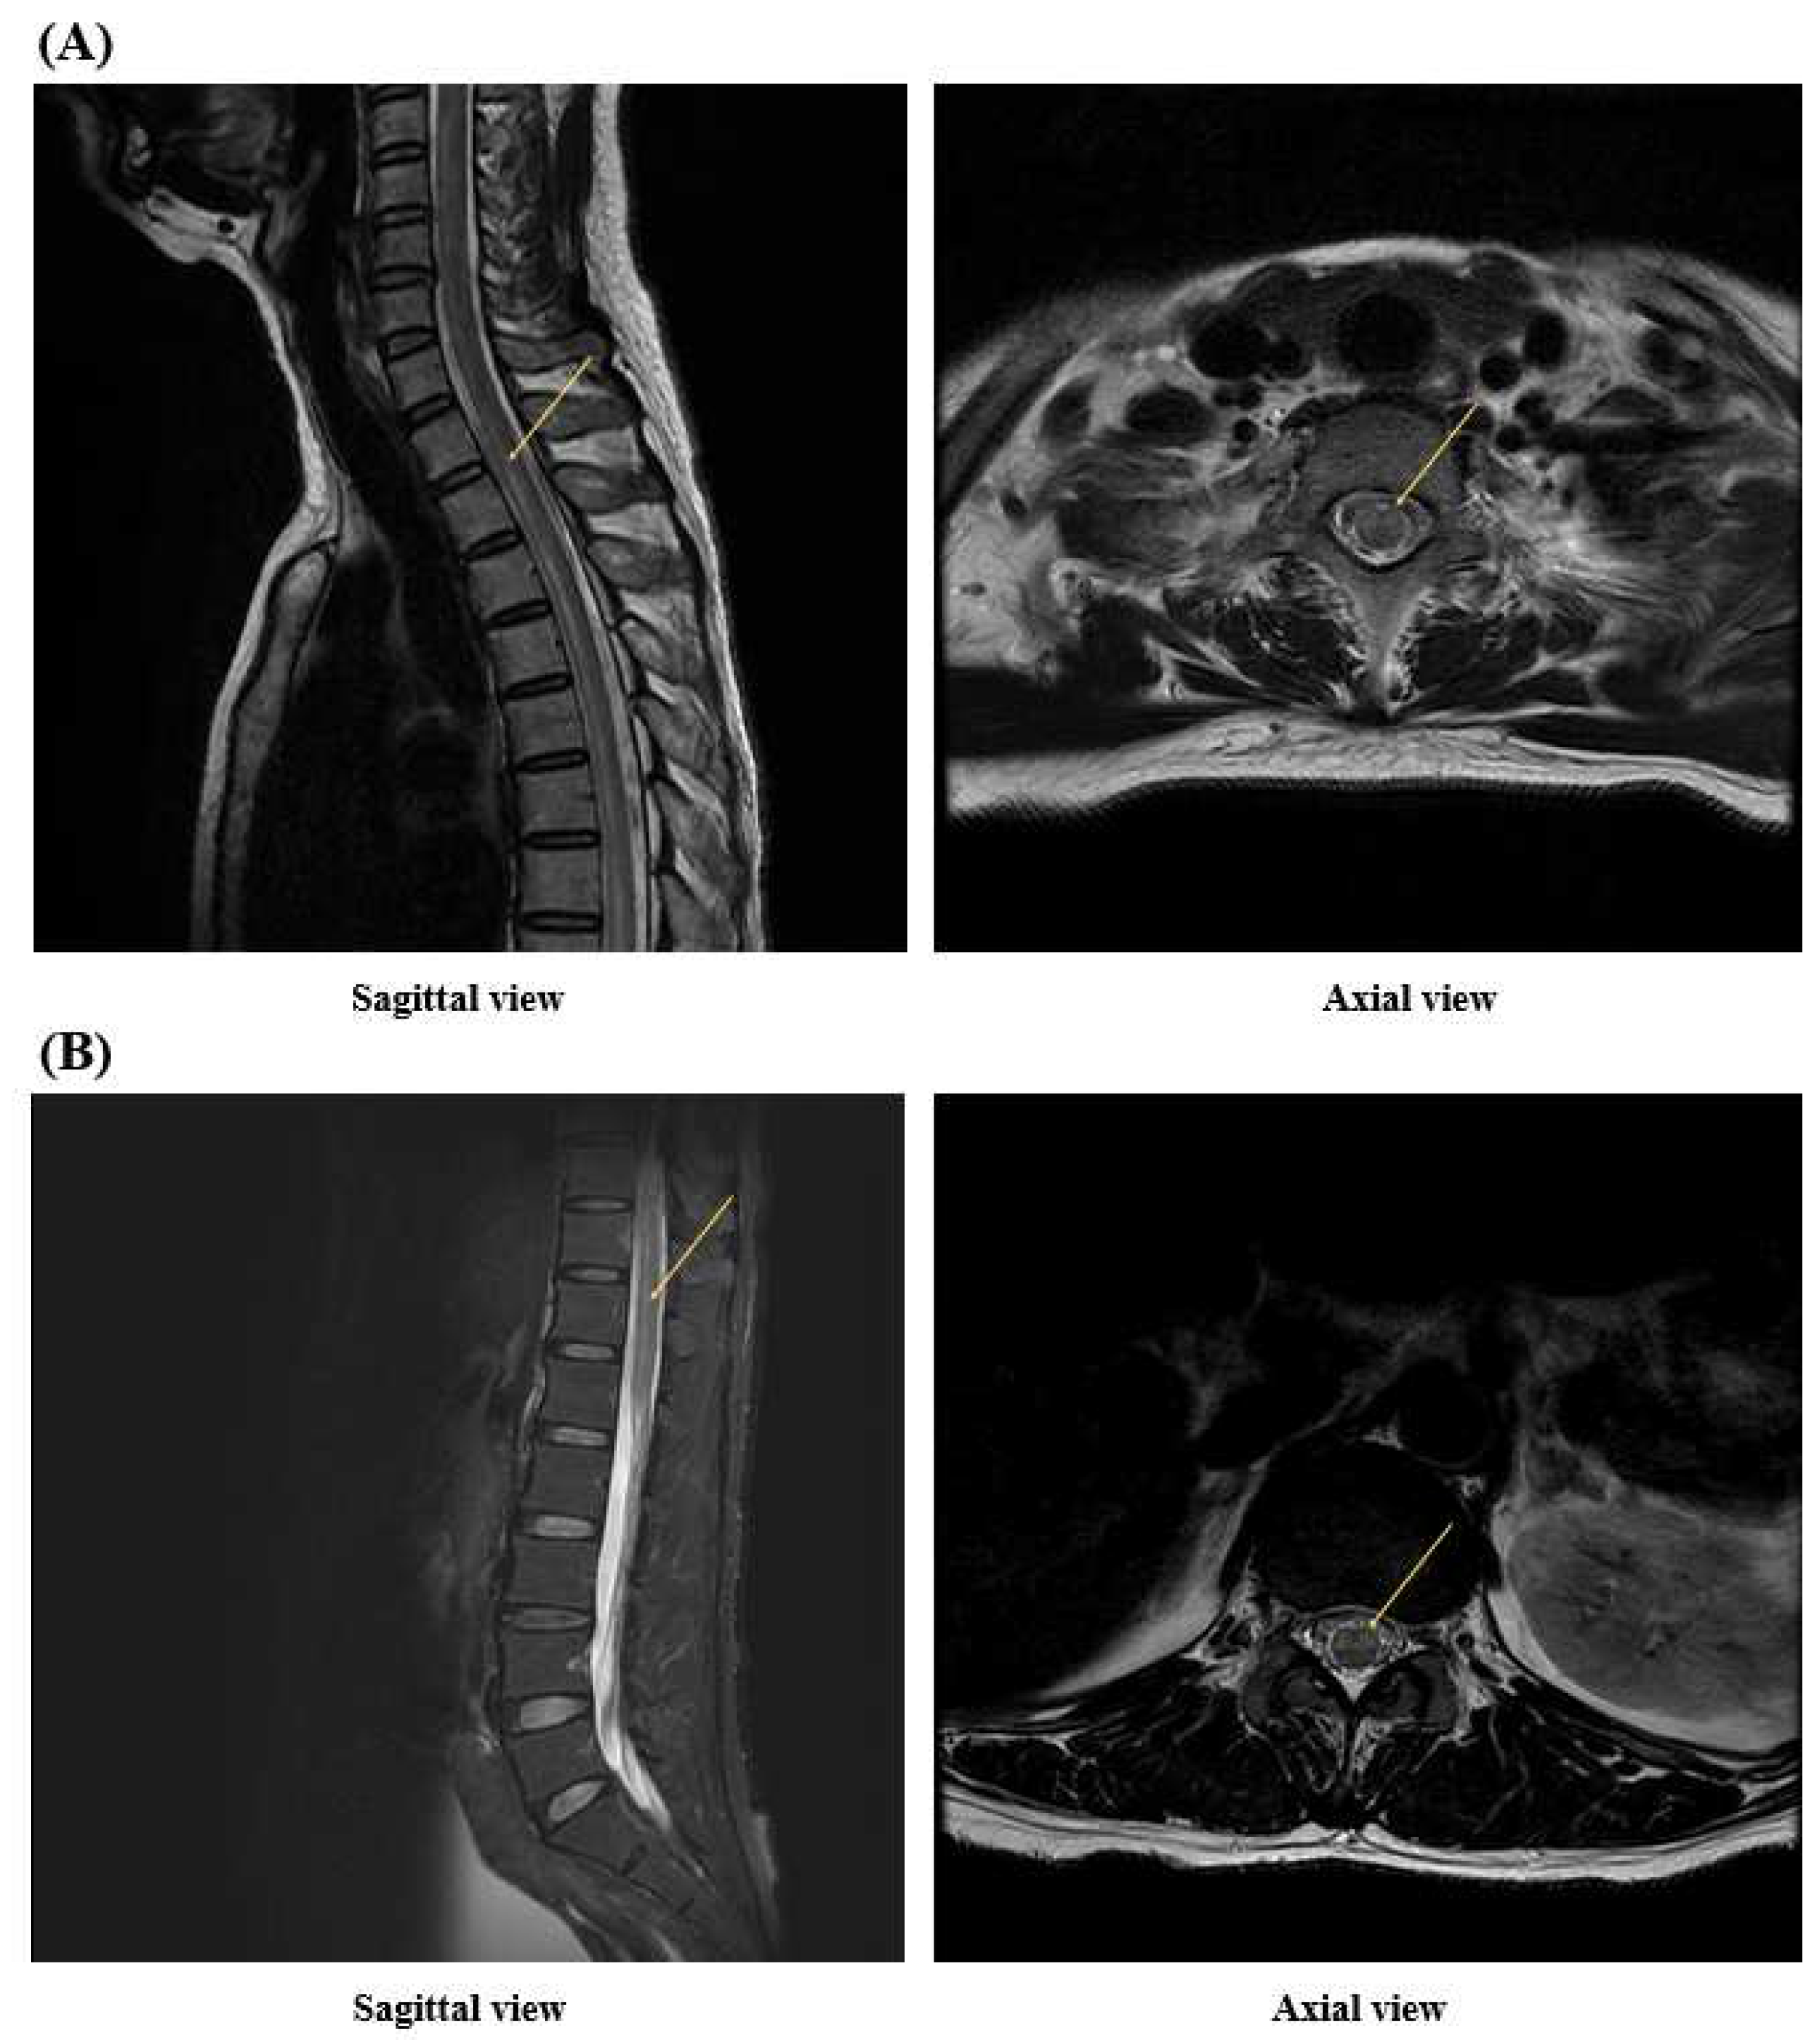

2. Case Presentation